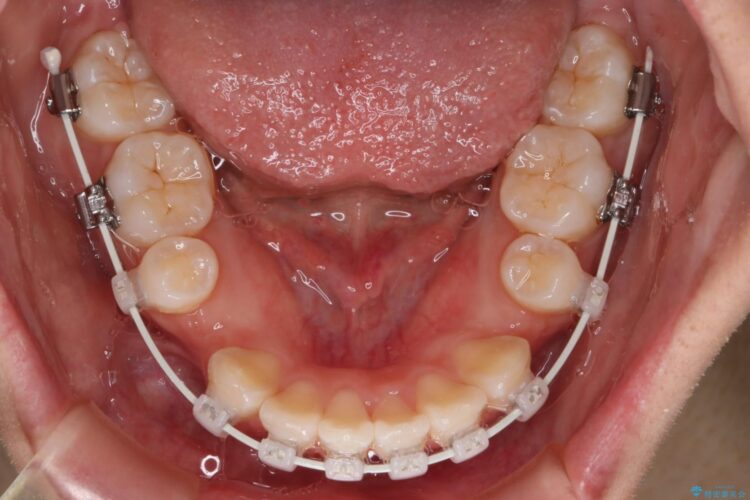

上下4番目の歯を抜歯してガタつきを改善しながら口元を下げる治療計画を立てました。

抜歯矯正で口元を下げたことで、Eラインが大変綺麗になりました。